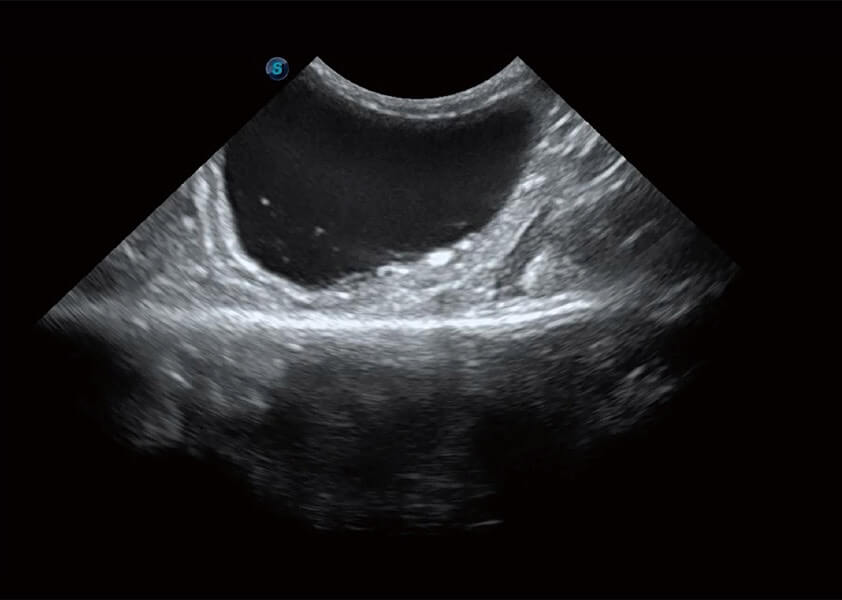

优异的基础图像

(犬)胆囊泥沙

(猫)膀胱结晶